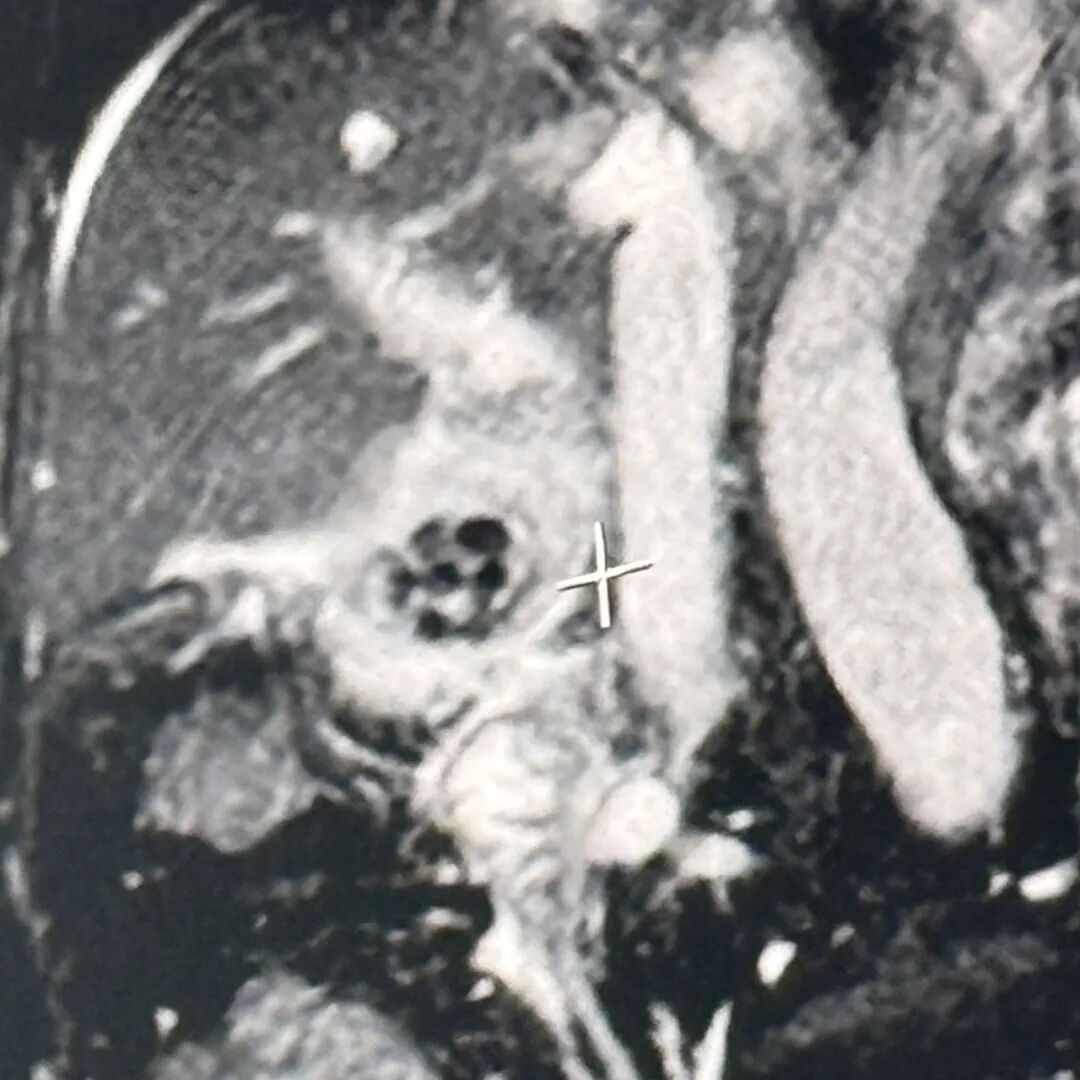

检查结果显示血常规炎症指标升高,影像提示胆囊结石、胆囊炎,胆总管、肝门部胆管、左肝胆管扩张。明确诊断为胆总管结石、胆囊结石伴急性胆囊炎

胆总管结石分为两类,一类是结石在胆总管里自己形成的(原发性);另一类,也是更常见的一种,是胆囊里的小结石通过胆囊管“掉”进了胆总管这个更粗的主管道里(继发性),陈爷爷的情况就属于后者。

胆总管是胆汁流入肠道的“唯一通道”,这里被结石堵住,后果比在胆囊里要严重得多,堪称“交通要道上的致命路障”,可能导致梗阻性黄疸、急性胆管炎、急性胰腺炎等严重并发症,危及生命。

经过全面评估,团队最终决定实施ERCP+EST+ENBD+LC术,这是一种微创手术组合方案,通过内镜逆行胰胆管造影(ERCP)及相关技术取出胆总管结石,再行腹腔镜胆囊切除术(LC)切除病变胆囊。该方案避免了传统开腹手术的大创伤,更适合高龄、基础疾病多的患者。

手术由盛成胜主任团队开展,先将内镜经口腔插入至十二指肠降段,找到胆管开口后,行十二指肠乳头括约肌切开后,取出胆总管内的结石,最后置入鼻胆管引流。

“陈爷爷长期患有胆囊结石,反复引发胆囊炎致腹部疼痛,后结石落入胆总管造成了胆总管梗阻,引起了更剧烈的疼痛,并导致了胆管和肝内胆管的扩张,最终造成了胆囊大面积化脓坏疽、炎症包裹的严重后果。”